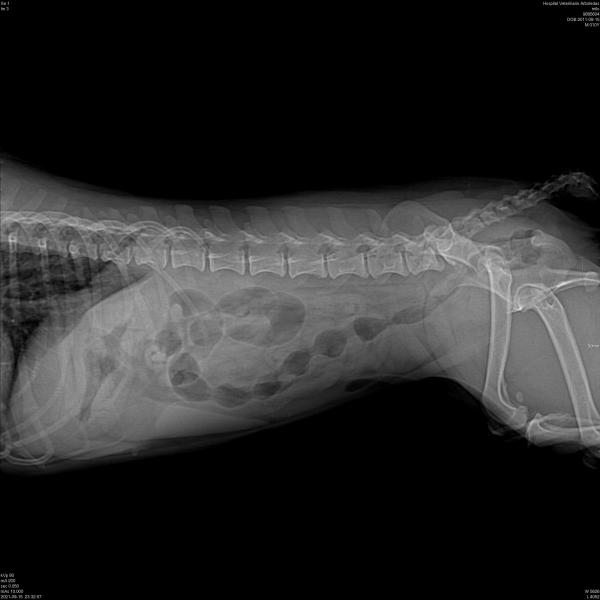

Hola. A mi perrita caniche le hicieron estas radiografías y me dicen que tiene líquido en los pulmones.